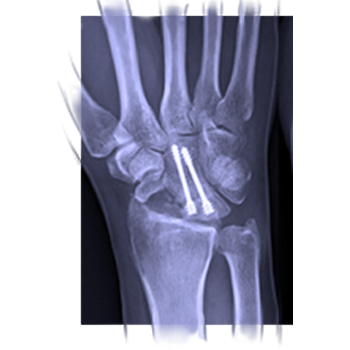

Bones and trauma

Camp 4

1.0 ECMECs

Look into several conditions, including fractures, cysts, and lesions